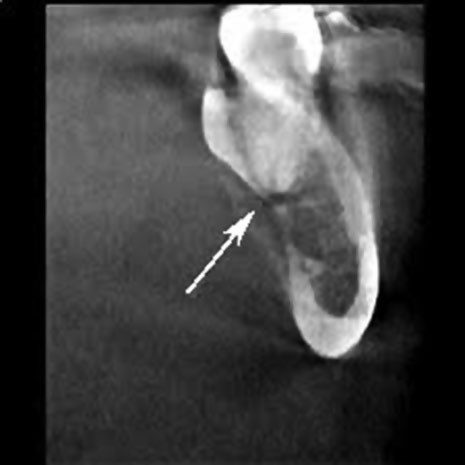

Hố dưới hàm chứa tuyến nước bọt dưới hàm, tạo ra 65% đến 70% nước bọt. Chân răng khôn thường nằm gần với hố dưới hàm.

Vỏ xương phía lưỡi ở khu vực này có thể mỏng hoặc mất hoàn toàn. Do đó, lực quá mức hoặc đặt sai vị trí có thể làm bật các mảnh chân răng hoặc thậm chí toàn bộ răng vào hố dưới hàm gần đó.